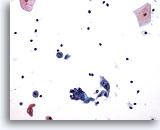

Figure 93

Bronchial wash

Low magnification shows atypical keratinized cells in squamous cell carcinoma. 20x

Bronchial wash

Low magnification shows atypical keratinized cells in squamous cell carcinoma. 20x

Figure 93

Bronchial wash

Low magnification shows atypical keratinized cells in squamous cell carcinoma.

20x

Bronchial wash

Low magnification shows atypical keratinized cells in squamous cell carcinoma.

20x